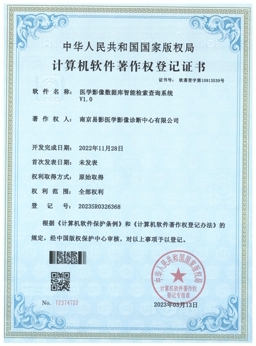

平台技术认证

权威认证保障

所有证书均由相关政府部门和权威机构颁发,确保我们的服务符合国家法规要求,为合作伙伴提供可靠的质量保障。我们承诺持续更新和维护各项资质认证,确保服务的合规性和专业性。

引入先进的AI辅助诊断技术,智能识别肺部结节、骨折等病变,计算冠脉钙化积分,大幅降低漏诊风险